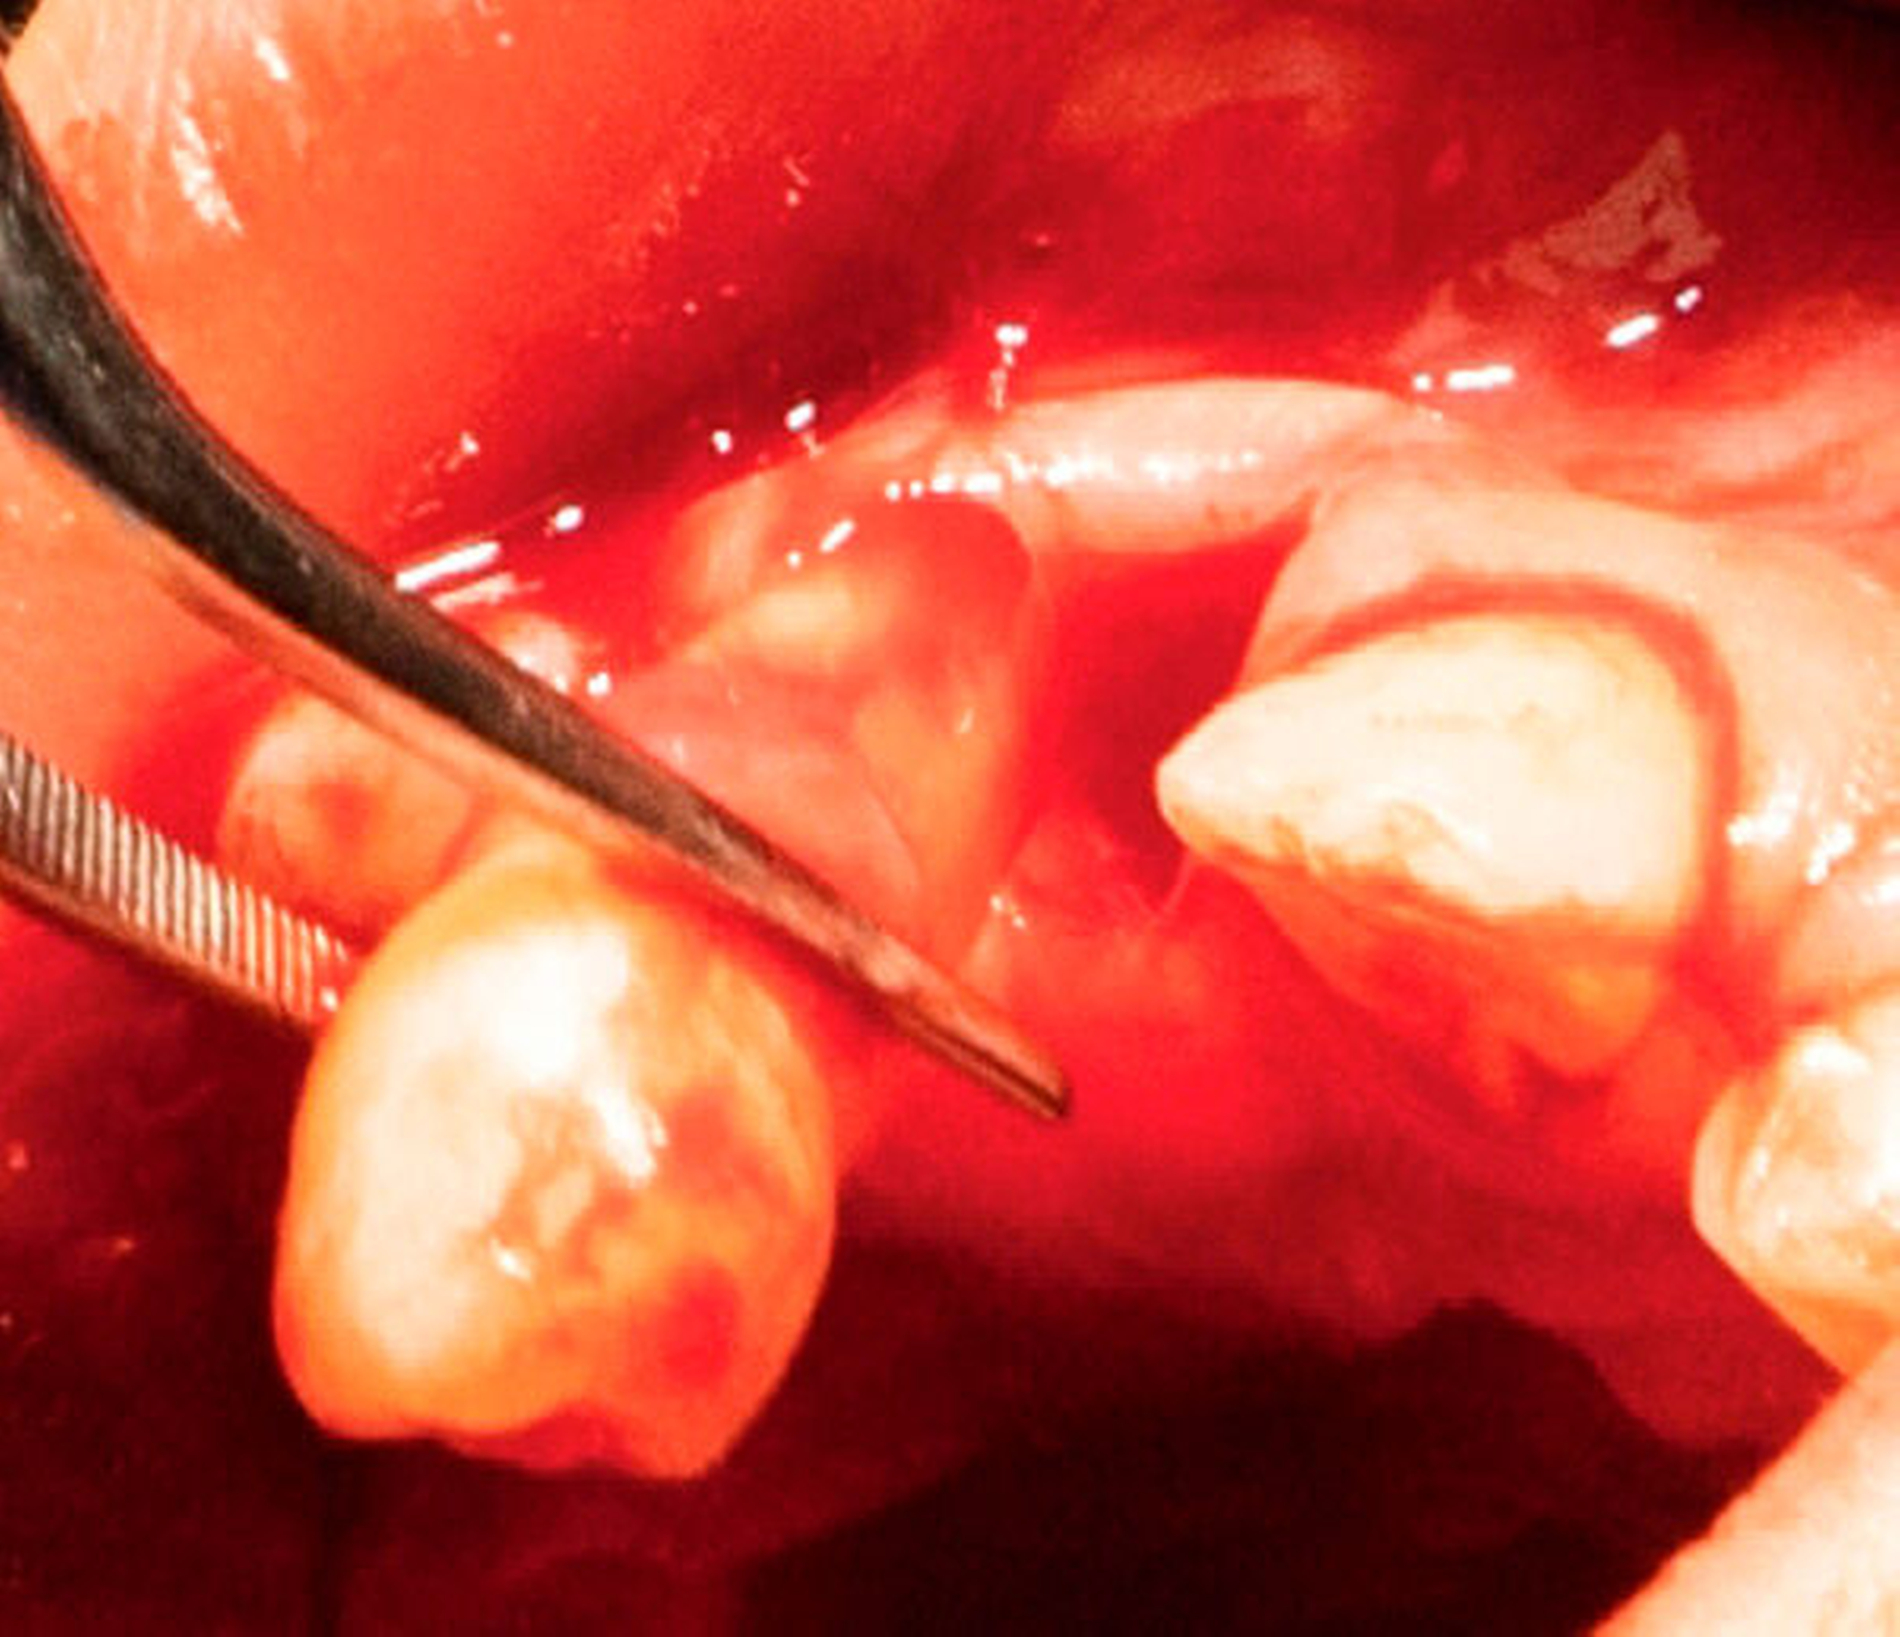

Das Wurzelwachstum des Transplantats sollte zum Zeitpunkt der Entnahme nicht mehr als zwei Drittel betragen. Dies kann eine operative Freilegung notwendig machen (Abb. 3).

Die große Regenerationspotenz des Zahnkeims, insbesondere während des Wurzelwachstums, ist Garant für deren Fortsetzung und den Erhalt der Vitalität in einer neu präparierten Alveole. Andreasen et al. [2007] bezeichnen die Neuformierung des Parodonts als den Schlüssel für eine erfolgreiche Transplantation. Zwei Drittel des Wurzelwachstums, ein offenes Foramen apicale (> 2 mm) und ein einwurzeliger Prämolar aus dem Unterkiefer gibt er als ideale Voraussetzungen für eine Erfolgsrate von 100 Prozent an. Eine weitere Voraussetzung ist die rasche Transplantation von der Spender- in die Empfängeralveole. Die Präparation der Schneidezahnalveole mit einem Dummy garantiert die optimale Passfähigkeit.